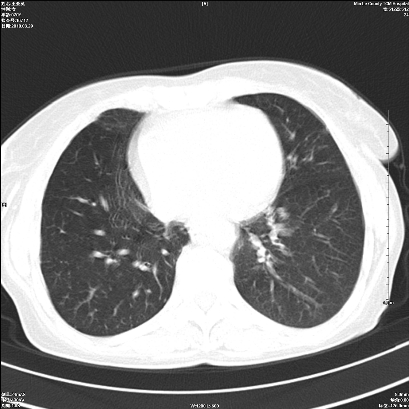

右肺上叶支气管开口阻塞,上叶呈不均匀致密影,右肺中下叶内见斑片状密度增高影,上叶见钙化点,纵隔内见钙化淋巴结,桶状胸,右下肺动脉增粗,残根征,意见:1.右肺中心性肺癌;2.右肺陈旧性结核;3.肺心病。

ct所见:右肺上叶肺不张,呈软组织密度影向肺门区聚拢,其内可见含气段支气管及细支气管影,病灶内尚可见钙化结节。右肺上叶支气管狭窄,段支气管壁可见钙化。右肺下叶背段、右肺中叶见不规则小片絮状影及纤维条索影,形态较僵硬。右肺中叶胸膜旁可见多个小结节影。纵膈内见钙化淋巴结。

分析:右侧胸廓及右肺体积缩小,说明病变时间比较长了,应该是有数年的时间了,如果是短期内出现的肺不张,只会引起纵膈向患侧移位,而不会引起胸廓的塌陷。不张的肺组织内可见含气支气管影,说明右肺上叶支气管没有完全中断,只是狭窄。右肺中叶、下叶散在不规则病灶,部分呈纤维化改变。纵膈内的淋巴结大部分钙化。因此,本例给我的感觉良性病变的可能是大。

结论:考虑右肺上叶支气管内膜结核合并右肺上叶肺不张;右肺中叶、下叶陈旧性肺结核改变。